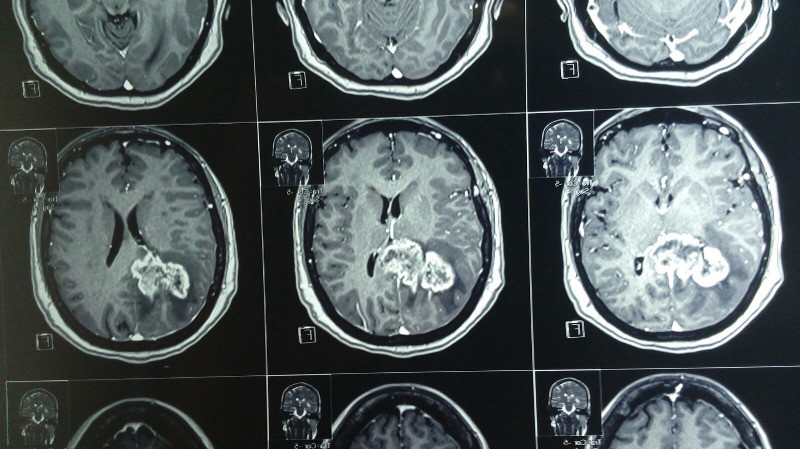

Tumoración pineal con extención superior lateral derecha

Paciente femenina de 55 años con tumoracion pineal con extencion superior lateral derecha